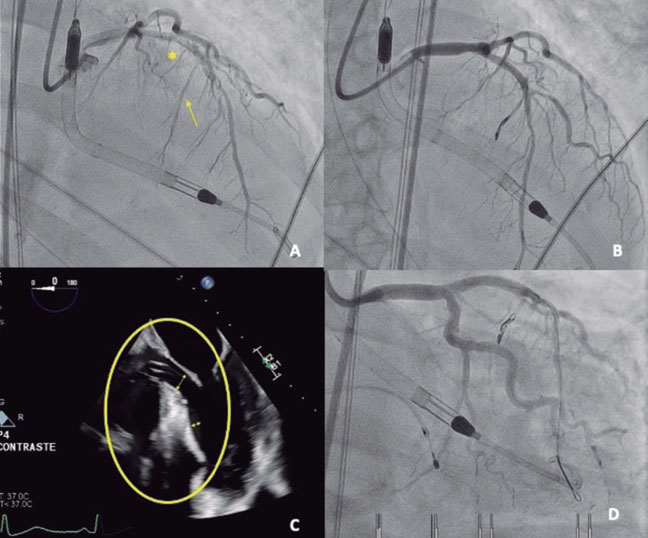

Una mujer de 77 años ingresó por síndrome coronario agudo sin elevación del segmento ST de clase Killip-III. El cateterismo emergente mostró una lesión crónica no oclusiva en la descendente anterior media, que se trató. La evolución, tras recuperar la fracción de eyección del ventrículo izquierdo, sugería síndrome de tako-tsubo (figura 1A,B).

A pesar de la administración de fluidoterapia y esmolol para disminuir la obstrucción dinámica del tracto de salida del ventrículo izquierdo (ODTSVI), progresó a shock cardiogénico SCAI-D y requirió vasopresores, intubación e implante de balón de contrapulsación aórtico en ratio 1:3 para evitar exacerbar la ODTSVI. Ante el continuo deterioro, se decidió escalar a Impella CP (Abiomed, Inc., EE.UU.) como puente a la recuperación. Se descartó afección mitral orgánica y, considerando la insuficiencia mitral secundaria al movimiento sistólico anterior (figura 1C, vídeo S1), se planificó una ablación septal emergente.

El implante del dispositivo Imp ella-CP (figura 1D, asterisco) ajustando un flujo de 2,4 l/min (P4) para evitar la succión, produjo una mejora hemodinámica y respiratoria inmediata, con disminución de la insuficiencia mitral (figura 1E,F, flechas: onda S sistólica). Una segunda rama septal (RS) mostraba compresión extrínseca, y se seleccionó tras confirmar la irrigación septal (figura 2A, flecha: segunda RS; asterisco: primera RS). Se implantaron 2 coils (figura 2B) por la potencial reversibilidad, con reducción inmediata del flujo y reducción de ODTSVI.